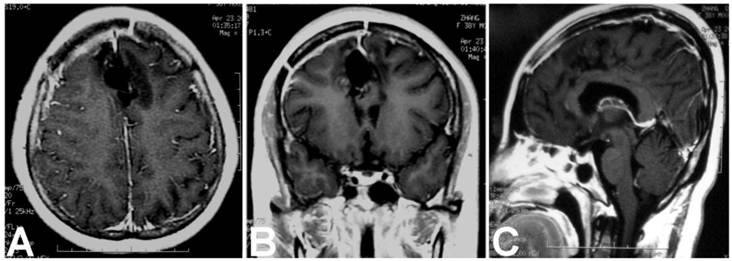

A 37-year-old female patient was admitted for intermitted headache of 6-year duration. She used to take painkiller (Aspirin or Ibuprofen Sustained-Release Capsules) to relieve the headache, but recently it had not been effective as before. On physical examination, except for mild papilledema, no positive neurological signs were found. Head CT scanning revealed a round lesion between two frontal lobes, with homogenous hypo-density containing a small region of hyper-density in its rim (Fig. 1 A). On MRI, the lesion was 3.5cm×3.6cm×4.5cm in volume and located above the corpus callosum and between the both frontal lobes. It displayed uniformed hypo-intensity on T1WI and hyperintensity on T2WI, with capsule enhancement on contrast images (Fig. 1 B, C and D). During surgery, left frontal craniotomy was performed and inter-hemispheric approach was used to reach the lesion. The lesion was enveloped by a thick white capsule, which was subsequently proved to be a part of the cerebral falx. We firstly cut the capsule at the top end and evacuated its soft, yellowish and greasy content, and then its capsule and the involved dura mater were totally removed. In the capsule wall, a little piece of bone-like material was found (Fig. 1 E). Patho-histological examination of the removed tissues demonstrated the lesion contained well differentiated adipose tissue, mature bone and keratin-producing squamous epithelium (Fig. 1 F and G), which were consistent with the diagnosis criteria of a mature teratoma. Postoperatively, the patient recovered uneventfully and was discharged one week later. At three years of follow-up, neither neurological deficits nor recurrence signs was found (Fig 2 A, B and C).

Postoperative enhanced MRI showed no residual or recurrence of the teratoma at three years of fellow up. A. Axial image; B. Coronal image; C. Sagittal image.